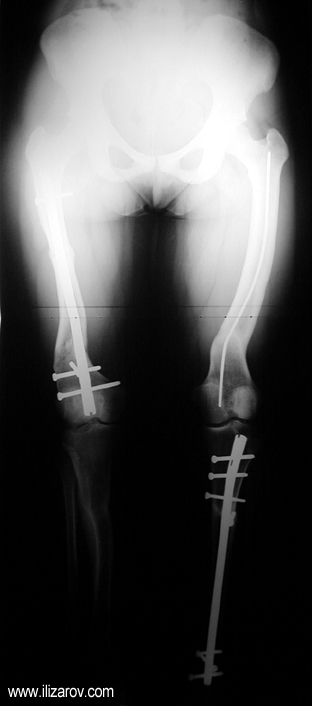

Because the deformity caused by hypophosphatemic rickets is very close to the growth plate, a significant deformity and malalignment occurs. For that reason, more than one deformity centers (CORA) are found at preoperative evaluation, and osteotomy at more than one level is required to correct the deformity. The most frequently used methods to correct the deformity are acute or gradual deformity correction using the Ilizarov method or unilateral external fixator. In the ‘fixator assisted nailing’ technique, which is applied in our department, the deformity is corrected in an acute fashion with the help of an external fixator, and the extremity is stabilized by an intramedullaru nail. The external fixator is removed before the end of the surgery if no gradual lengthening is planned postoperatively. If lengthening (over nail) is planned, the fixator is removed after the completion of the lengthening procedure. As a result, the risk of pin tract infection is eliminated, correction loss and relapsing of the deformity (which are important problems in the treatment of hypophosphatemic rickets) are avoided, eary motion and full weight bearing are allowed, and comfortability of the patient is improved because the duration with external fixator is decreased.